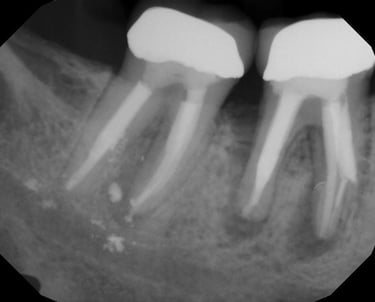

Se identifica si hay fracturas en la raíz del diente, que pueden causar dolor, infecciones o problemas de estabilidad dental. Se utilizan radiografías y exámenes clínicos para este diagnóstico.

Evaluación de fracturas radiculares

Se analiza el estado de dientes que han recibido tratamientos endodónticos anteriores para verificar su éxito y determinar si se necesita un retratamiento.

Evaluación de dientes con tratamientos previos